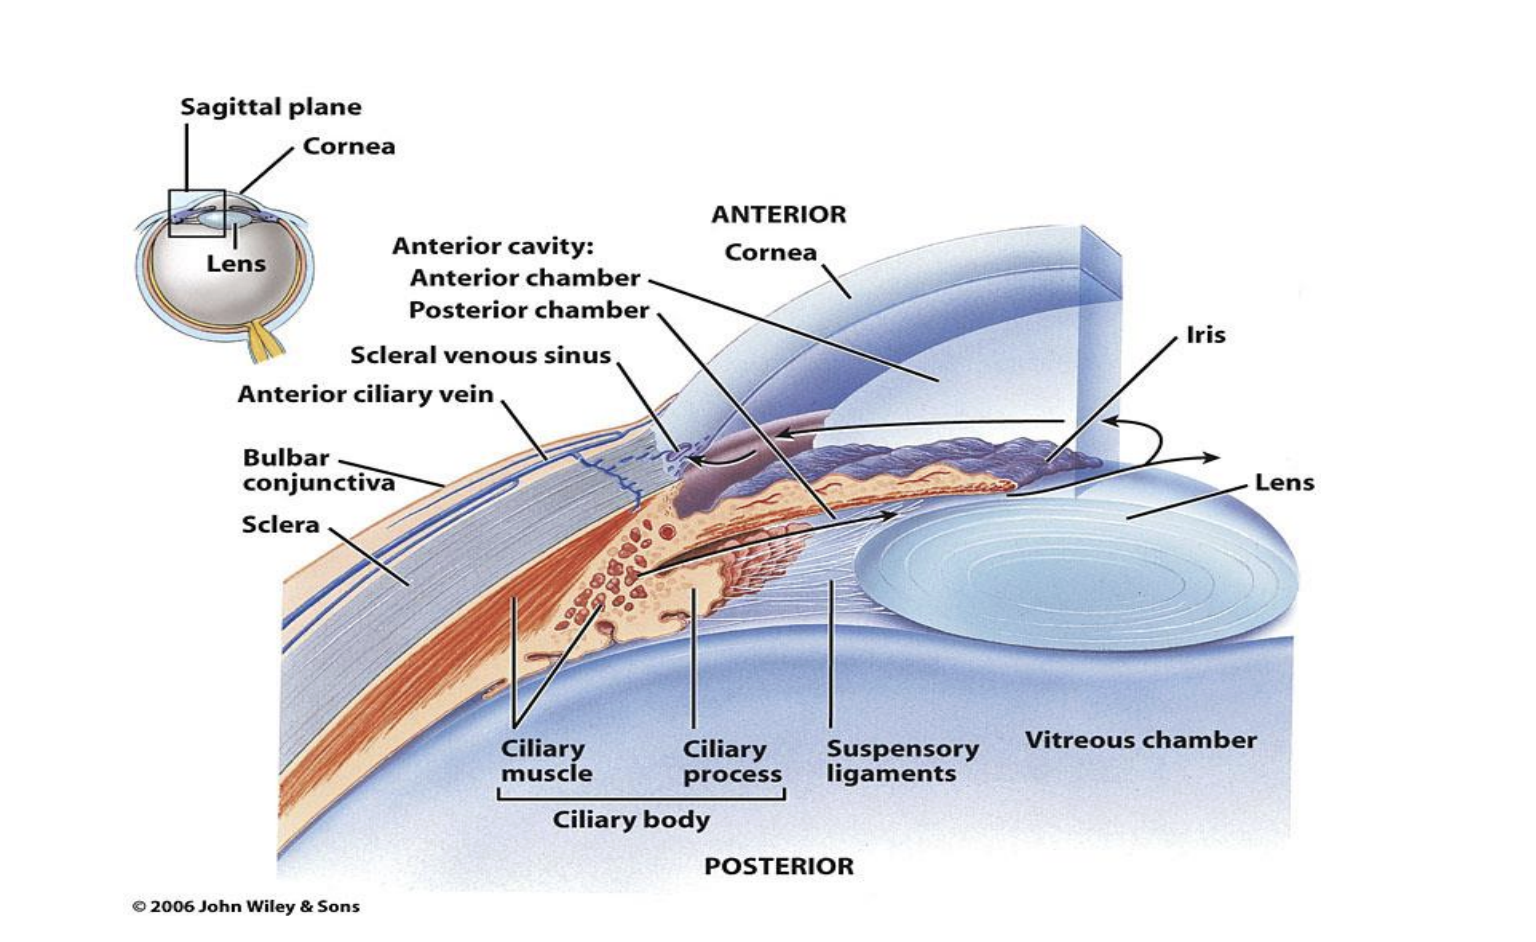

Parts of the Eye

Fibrous layer/tunica: sclera and cornea

Vascular layer/tunica or uvea: choroid, ciliary body, iris

Inner layer/tunica: retina

Lens

Suspensory ligaments

Optic nerve

Optic disc

Anterior chamber (between cornea and iris)

Posterior chamber (between iris and lens)

Vitreous chamber (between the lens and the retina)